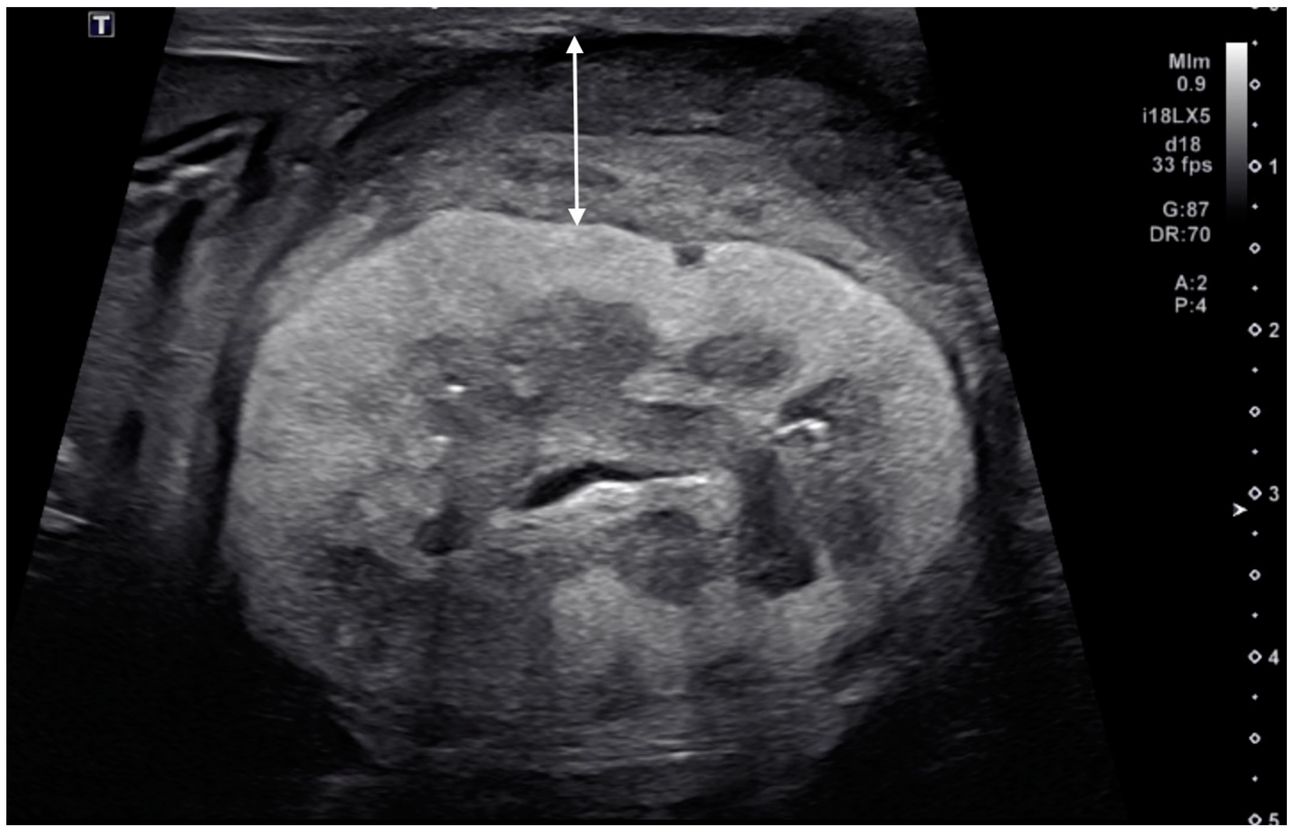

Ultrasonographic image of a kidney with primary renal carcinoma (case 6, left kidney). A thick, circumferential, heterogeneously mixed isoechoic to hypoechoic subcapsular thickening (double-headed arrow) was present. The renal cortical and the renal capsular margins were irregular. Note the diffuse, markedly hyperechogenic renal cortex.

Six cats met the inclusion criteria, showcasing a mix of primary renal carcinoma, metastatic carcinomas, and presumed metastatic carcinomas from primary pulmonary sources. Ultrasonographic findings indicated that metastatic subcapsular thickening lesions were relatively thin, focal, homogeneous, and hypoechoic, while primary ones were circumferential and heterogeneous. Abnormalities in renal parenchyma, such as hyperechoic cortex with hypoechoic striations, were observed in most affected kidneys. This study is the first to document ultrasonographic subcapsular thickening in feline kidneys due to metastatic carcinoma.